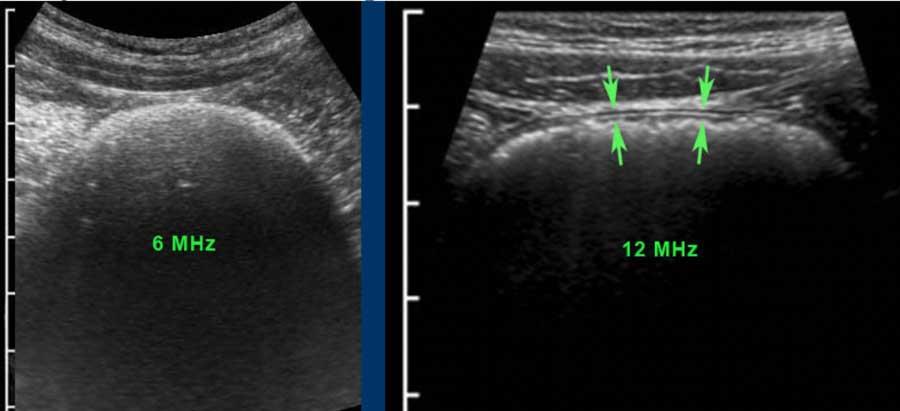

Khi sử dụng đầu dò tần số cao, ba lớp giữa, bao gồm lớp niêm mạc sâu, lớp dưới niêm mạc và lớp cơ (đen-trắng-đen) luôn luôn hiển thị rõ ràng.

Ở bệnh nhân này với tình trạng ứ phân nặng, cấu trúc thành ba lớp chỉ có thể được nhận diện bằng đầu dò 12 MHz.